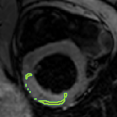

4.2 Visual assessment

We select the case that achieves the highest and lowest dice score for visual assessment. Fig. 4 shows example segmentation results where the proposed method achieved the highest agreement with the ground truth delineations. Fig. 5 shows example segmentation results where the proposed method achieved the lowest agreement with the ground truth delineations.